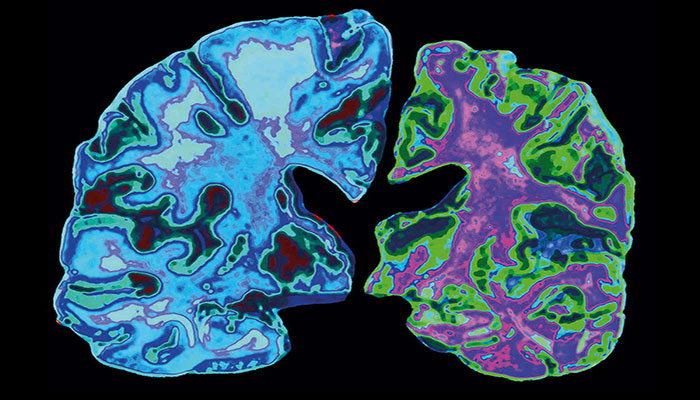

Prof Wasey said Alzheimer’s was a neurodegenerative disease and most common type of dementia. “It is a progressive disease beginning with mild memory loss and possibly leading to loss of the ability to carry on a conversation and respond to the environment. “Alzheimer's disease involves parts of the brain that control thought, memory and language,” he added.